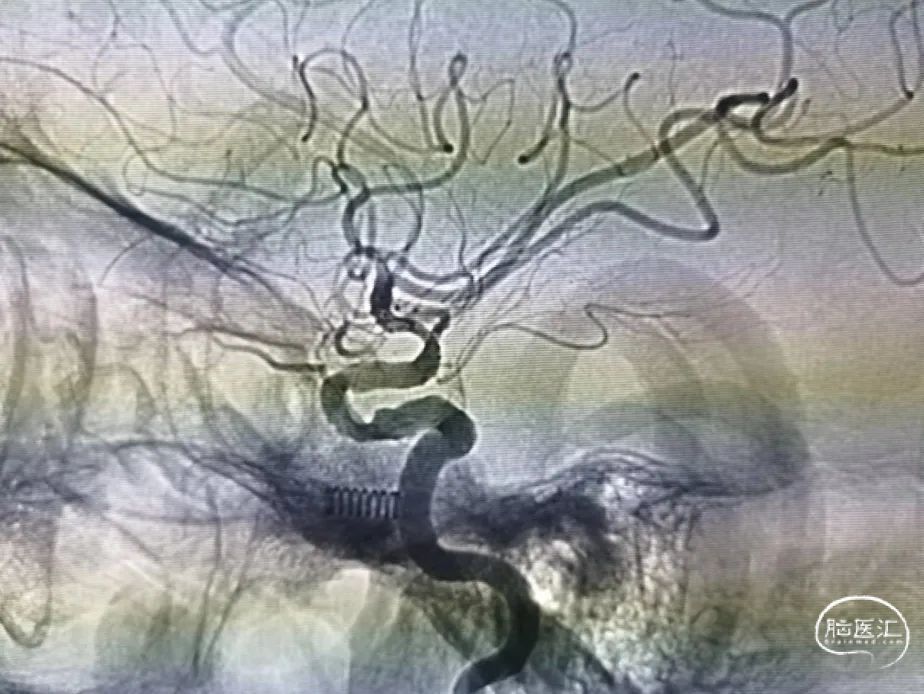

患者取平卧位,全麻满意后,术区常规消毒铺巾,右股动脉行Seldinger穿刺,置入6F动脉鞘,静脉肝素化。造影见:1.右侧颈内动脉C1段成角,并血管中度狭窄,C4段管腔瘤样凸起,前交通开放,可见双侧大脑前动脉显影;2.右侧锁骨下动脉中重度狭窄,腋动脉重度狭窄,椎动脉开口中重度狭窄;3.左侧颈内动脉C1段成角并血管中度狭窄,A1发育性纤细,M1重度狭窄,并成角畸形(Mori C型),颞干发自狭窄段并重度狭窄,远端大脑中动脉显影差(TICI 2b),大脑前动脉通过软膜支向中动脉代偿;4.左侧锁骨下动脉中度狭窄,椎动脉开口中度狭窄;5.脑血管符合多发硬化表现。超滑泥鳅导丝携带6F Envoy选入左侧颈内动脉,管头位置满意后撤出泥鳅导丝,造影见左侧大脑中动脉重度狭窄,并成角畸形(Mori C型),远端大脑中动脉显影差(TICI 2b),大脑前动脉通过软膜支向中动脉供血区代偿供血。

选择合适工作角度,路图指引下,Synchro微导丝携带SL-10微导管小心通过狭窄段,微导管跟入远端血管,回抽见返血,冒烟明确微导管位于真腔内,交换300cm Transend微导丝,撤出微导管。

沿微导丝送入Gateway 1.5mm×15mm球囊一枚,跨越狭窄,造影见正向血流消失,缓慢充盈球囊至6 atm,维持20s后缓慢抽瘪球囊,冒烟未见造影剂渗出,造影见血管狭窄改善,XperCT未见出血。

回撤球囊至导引导管,维持高压肝素水滴注,等待10min后再次造影见血管回弹较明显,遂抽瘪球囊状态下跟入Gateway至狭窄远端,撤出微导丝,沿Gateway输送管送入Atlas 3mm×15mm支架一枚,跨越狭窄释放,见支架展开良好,正向血流明显改善,颞干血流较术前无明显变化,撤出输送系统。等待10min后再次造影见血流通畅,XperCT未见出血,给予欣维宁泵入,结束手术。